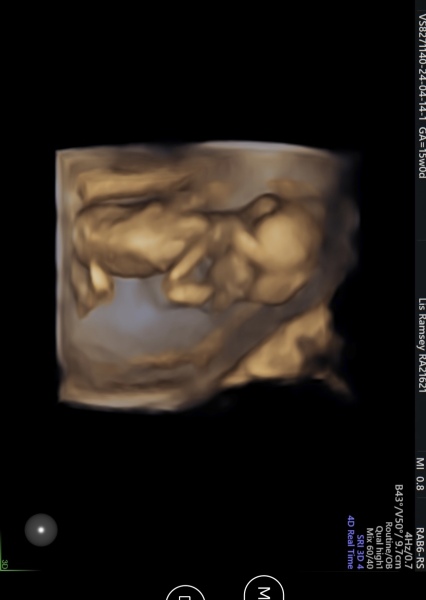

Forgot to mention if anybody is around 15 weeks like me, we got a sneak peak of what our little one looks like in 4d! The lady who scanned us reccomended a 4d scan at 24 weeks to get the best pictures ❤️

@PineappleBella awww how cute!! ❤️ Congrats on your baby boy 💙 We've got an early sexing scan booked for when I'll be around 15 weeks and I think we get a sneak peak in 4d too! Xxx